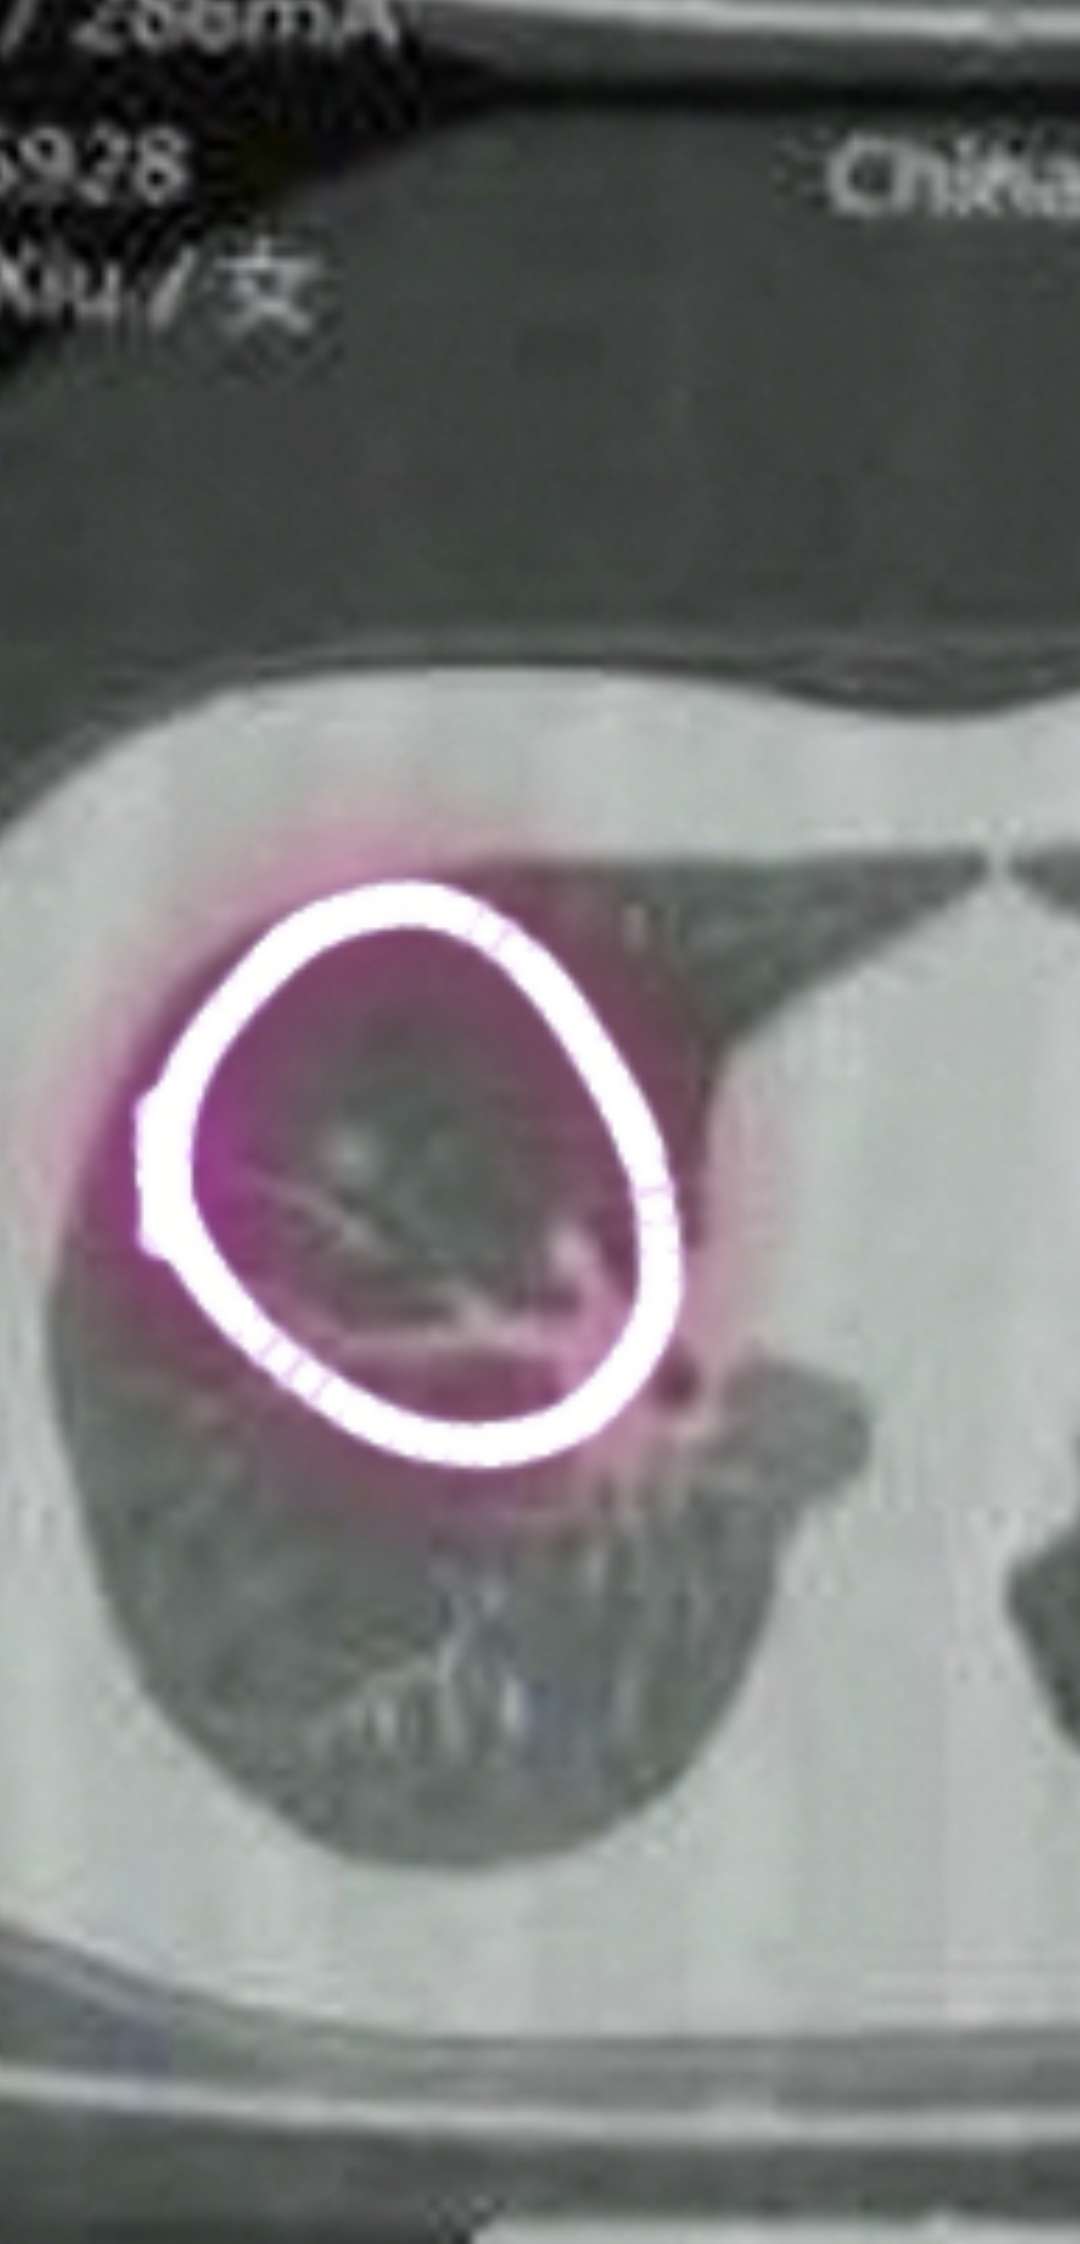

陈波医生我的意见是积极外科手术拿掉。此图像一个日冕,中间的日体和周围的光晕之间密度区分比较明显了,说明中央部分密度较高,有可能有局部浸润

有点像微乳头状磨玻璃结节